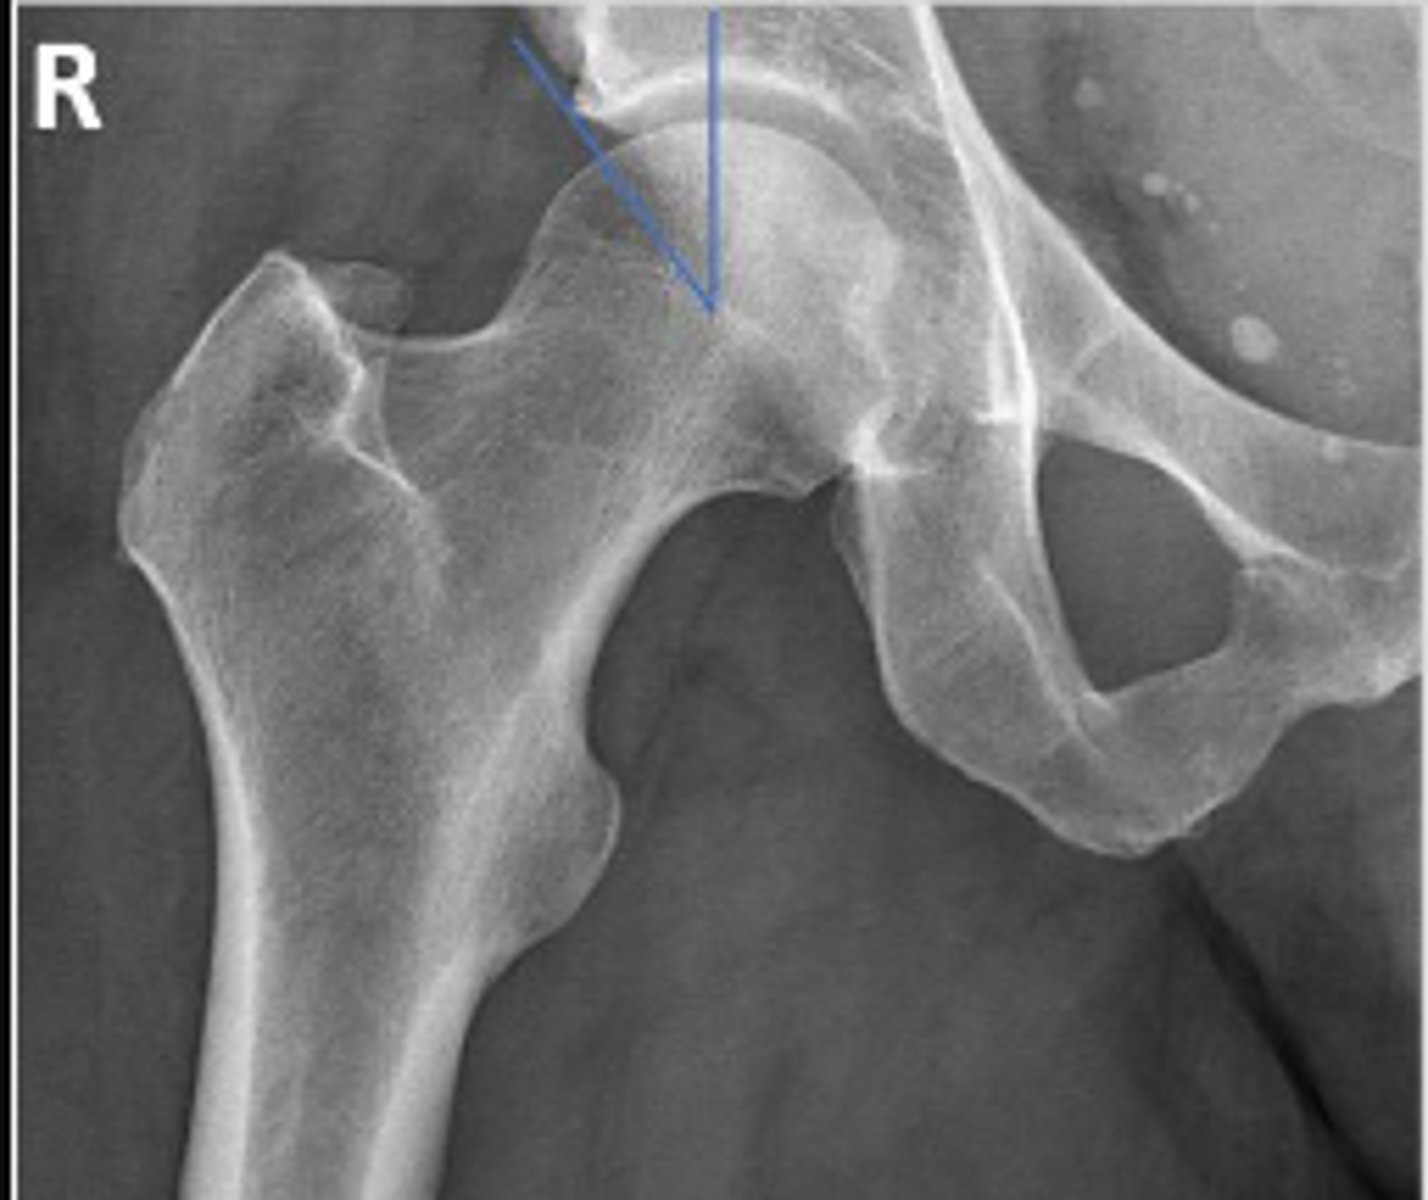

Right AP hip

What is the name of the radiographic view?

Center edge angle

What is the name of the assessment?

20-40 degrees

What is the normal range for this assessment?

A vertical line is drawn upwards from the center

of the head of the femur.

The second line is drawn from the center of the femur head to the outer superior-lateral aspect of the acetabulum

What are the osseous landmarks for this assessment

No (normal measurement is 20-40 degrees)

Is the measurement within normal limits?

Acetabular dysplasia

Developmental dysplasia of the hip

Name 1 condition that may result in a measurement <20 degrees?

AP pelvis and AP hip views

Name 2 radiographic views for this assessment?